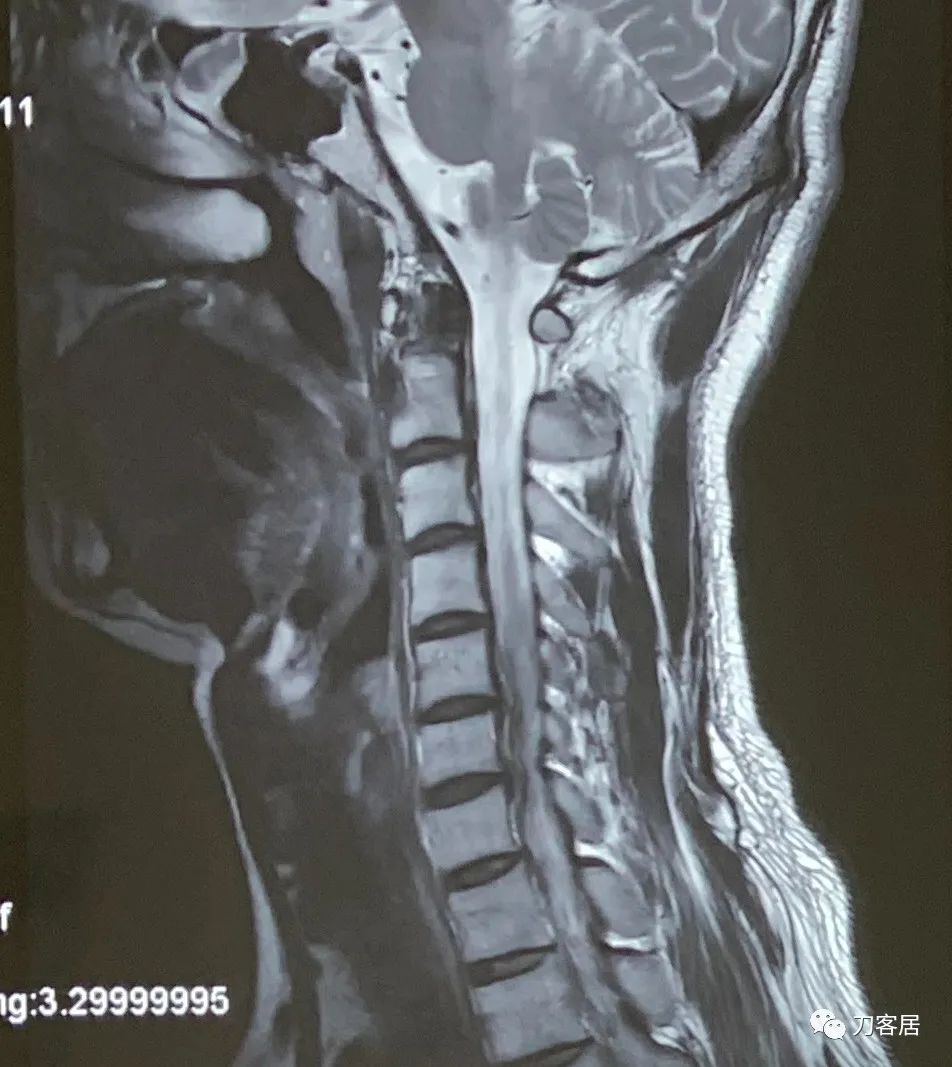

图2. 20221212上海华山医院颈椎MRI02,局部放大的一个切面,可看到颈5-6较大的椎间盘突出,进入椎管。

图3. 20221212上海华山医院颈椎MRI03,颈5-7椎间盘突出,椎管狭窄,脊髓受压。